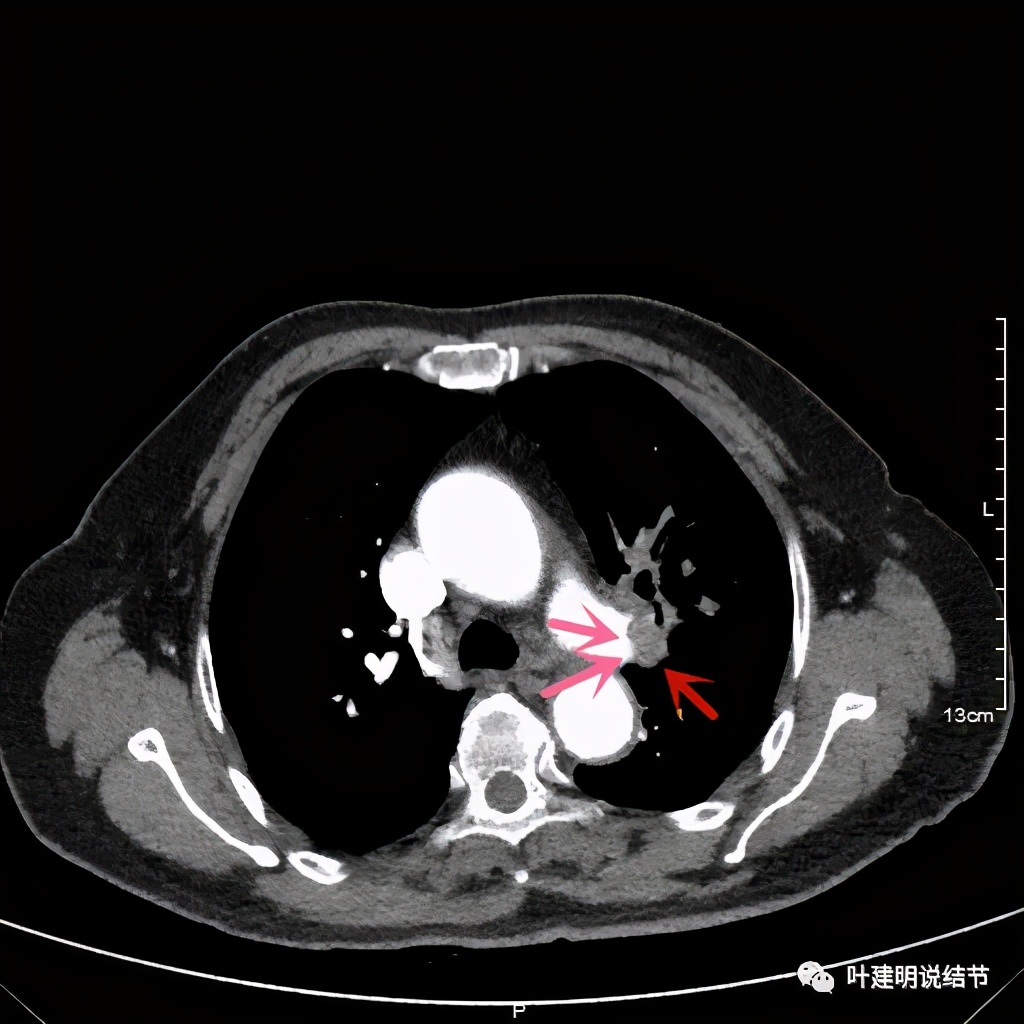

上图示肿瘤部位仍与肺动脉关系密切,似乎未能脱开,红色示肿瘤处